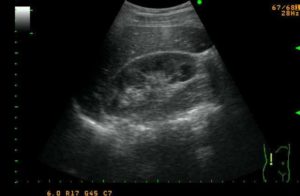

Пиелонефрит виден на УЗИ по разным признакам, зависящим от тяжести и длительности протекания болезни. Таким методом можно определить несколько форм воспалительного заболевания в почках. Картина острого процесса будет отличаться от результатов ультразвукового исследования хронического и локального воспаления.

Острый пиелонефрит

При острой патологии проведённое ультразвуковое исследование обычно показывает увеличенные размеры поражённой почки. Острый пиелонефрит видно на УЗИ изменением показателей, которые являются нормой для здорового органа. Определение нормальных показателей происходит по специальным таблицам, в которых учитывается пол и возраст больного.

При воспалении ограничивается подвижность органа. В норме смещение может происходить до 1,5 сантиметров.

Картина УЗИ показывает изменения и зависит от стадии развития пиелонефрита. Степень препятствия оттока мочи изменяет результаты обследования.

Обычно на мониторе аппарата пирамиды, находящиеся в корковом слое, выделяет тёмный цвет. При диагностике острого воспалительного процесса контрастность снижается, различия в цвете практически стираются.

Острое течение заболевания существенно нарушает кровоснабжение в органах. Картина выраженного снижения кровотока в органе на ультразвуковом исследовании фиксируется определённой цветовой гаммой. Отсутствует синий и красный цвет при диагностике в периферических участках коркового вещества почки.

Ультразвуковая картина при остром пиелонефрите

На УЗИ почек при остром пиелонефрите обнаруживается изменение размера органа, его подвижность, появляются сигналы различной эхогенности от воспаленной почечной паренхимы.

Изменяется почечная структура – она становится мелкозернистой.

При остром пиелонефрите за счет воспаления выражена отечность тканей,

Снижается подвижность пораженной почки при дыхании.

Зона паренхимы отличается эхосигналами различной плотности, что свидетельствует о наличии мелких абсцессов.

Отмечается повышенная плотность слизистой лоханки.

Часто воспаление поражает околопочечную клетчатку.